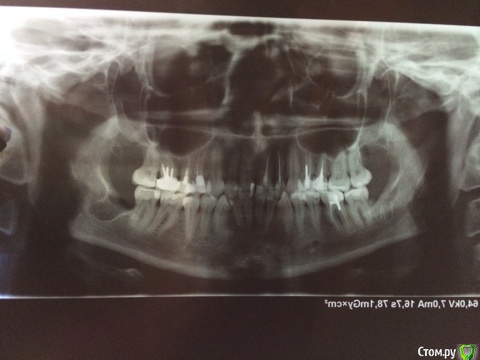

skazzkina Опубликовано 26 августа, 2015 Поделиться Опубликовано 26 августа, 2015 Здравствуйте, уважаемые врачи! Прошу консультации, после удаления всех восьмерок осталось уплотнение/похоже, рубец, на месте, где были швы/, сказывающееся на симметрии лица! 13.08.2015 мне были удалены 4 восьмерки. Удаление происходило в стационаре, под общим наркозом. Далее все стандартно: стационар, отеки, температура, антибиотики-уколы, больничный и пр. 24.08.2015 мне сняли швы, рот стал более-менее открываться и появилась возможность чувствовать и наблюдать общую обстановку во рту. Верхние восьмерки зажили без проблем и дискомфорта не доставляют. А вот на нижних ощущаются уплотнения и рубцы, на месте, где были наложены швы. Причем на одном зубе рубец с внутренней стороны, ближе к гландам - он приносит дискомфорт при сглатывании и ощущается при открытии рта. На другом нижнем - и он беспокоит больше всего - рубец с наружной стороны, между челюстью и щекой, отчего в данном месте ощущается уплотнение и это ВИЗУАЛЬНО ЗАМЕТНО! Это уплотнение я чувствую во время разговора, когда улыбаюсь и пр. И его просто заметно, как припухлость на щеке! При этом общие отеки спали. Прошу подсказать, есть ли шанс, что данный рубец заживет или рассосется, разгладится? Уплотнение пройдет? Или что мне теперь с этим делать? Я в панике... Прикладываю снимок,с деланный на 3 день после операции - все, что есть на руках. г. Самара. Буду благодарна любому ответу! Очень переживаю! Ссылка на комментарий

skazzkina Опубликовано 26 августа, 2015 Автор Поделиться Опубликовано 26 августа, 2015 корректный снимок Ссылка на комментарий